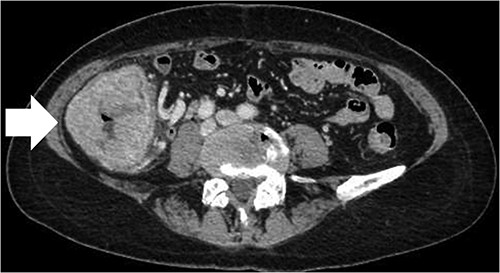

A 68-year-old female patient presented to our hospital with fatigue. She had a history of hypertension and hyperlipidemia. She appeared pale, but a physical examination revealed no other abnormalities. Laboratory findings revealed severe anemia, with a hemoglobin level of 8.8 g/dl. Abdominal computed tomography (CT) revealed tumors in the ascending colon and right lower kidney (Figs 1 and 2). Colonoscopy confirmed a Type 1 tumor in the ascending colon, and biopsies of this lesion revealed papillary adenocarcinoma. Preoperative TNM classification according to UICC classification was colon cancer, stage cT3N0M0, and right renal cancer, stage cT1aN0M0. Because both lesions were indications for robotic surgery, the patient underwent synchronous robotic right hemicolectomy and right partial nephrectomy using the robot da Vinci® Xi. Following the induction of general anesthesia, the patient was placed in the supine position. The first 8-mm trocar was inserted through the umbilicus using the Hasson method. The pneumoperitoneal pressure was maintained at 12 mmHg. Additionally, three 8-mm trocars were inserted under laparoscopic vision in the right lower abdomen, left lower abdomen and upper left abdomen, and a 12-mm trocar for assistance was inserted in the left abdomen (Fig. 3). The table was rotated slightly to the left and 10° head down. The robot was rolled in from the patient’s right side and docked. Robotic Arm 1 was affixed with bipolar forceps, Arm 2 had monopolar scissors and Arm 3 had a cadiere forceps. Starting with the inferior approach, the right ureter, gonadal vessels and Gerota’s fascia were preserved. The duodenum and pancreatic head were spared on the dorsal side, and the mesentery was mobilized.

Trocar placement for robotic right hemicolectomy with the patient in the supine position.